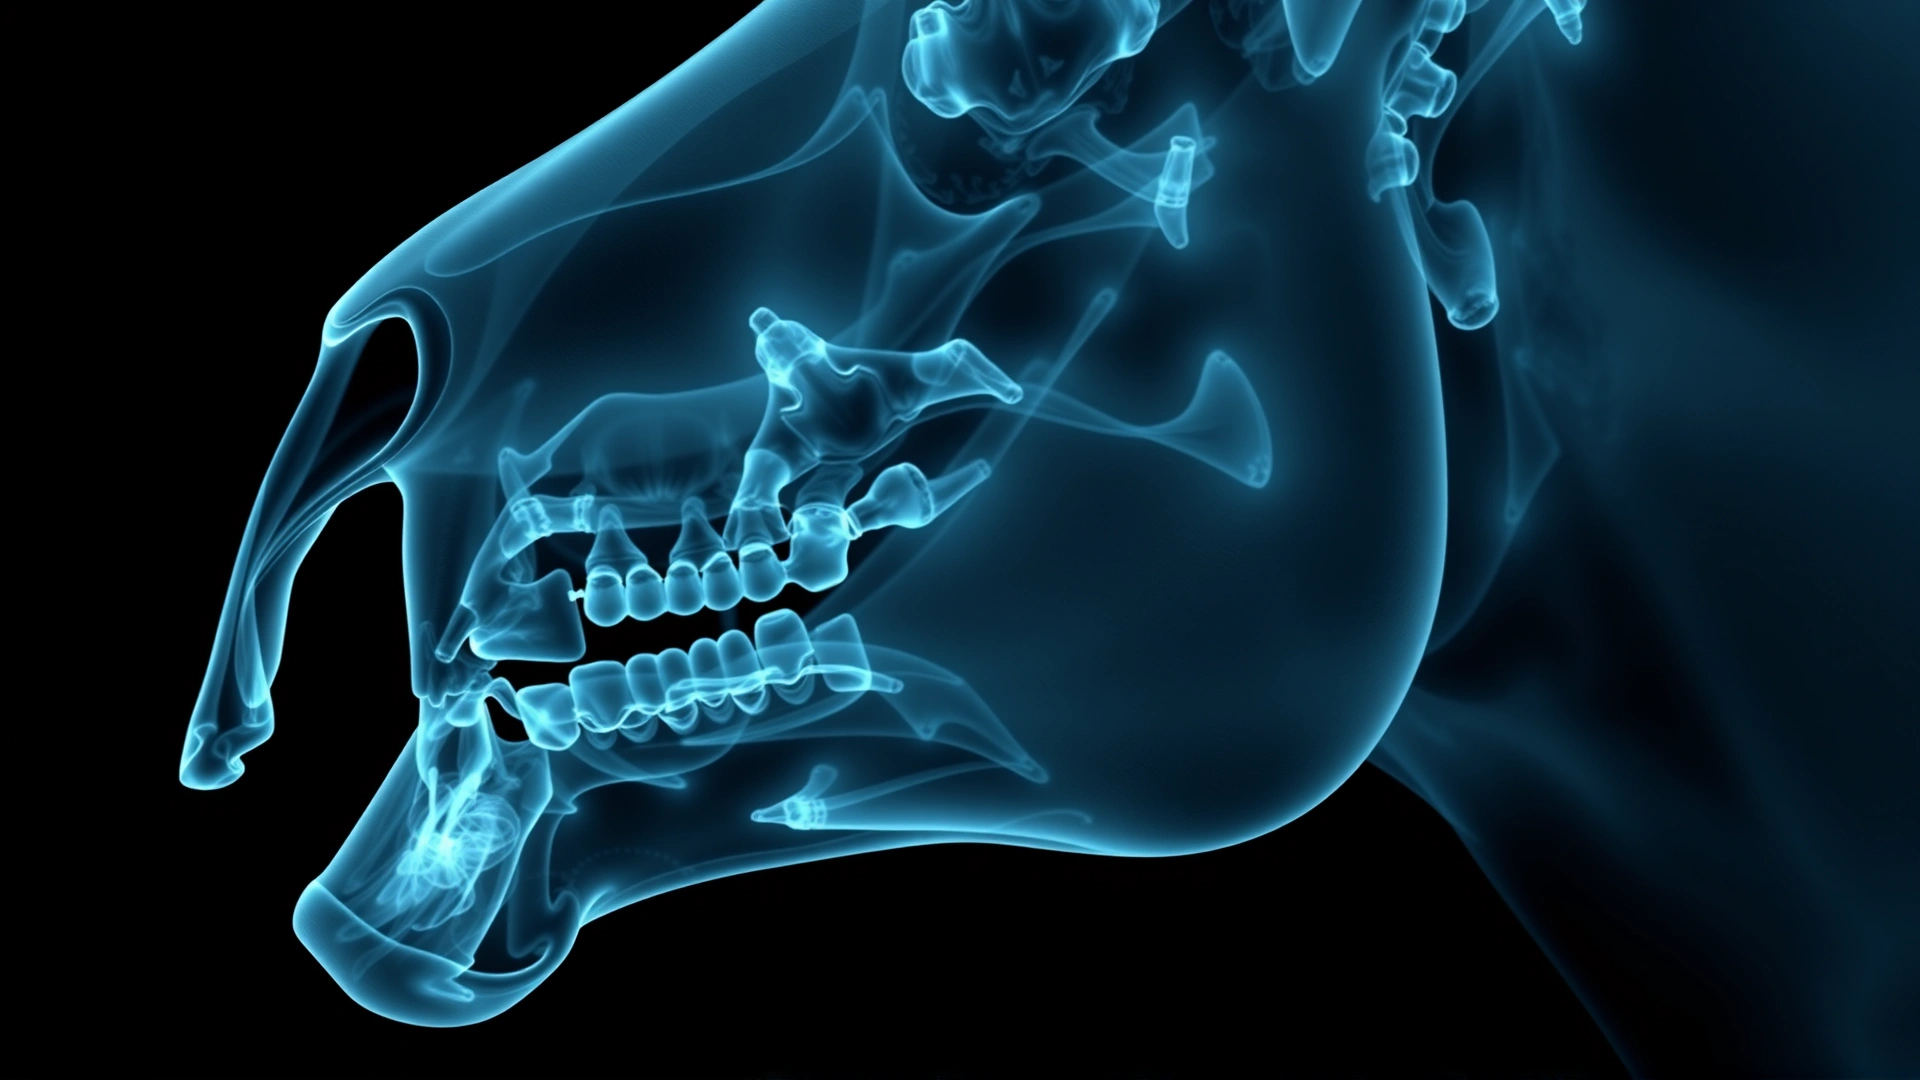

لا يمكن تأكيد الإصابة إلا بفحص بيطري متكامل يشمل:

- أحياناً تصوير بالأشعة السينية لتحديد موقع الغطاء بدقة والتأكد من عدم وجود جذور مكسورة